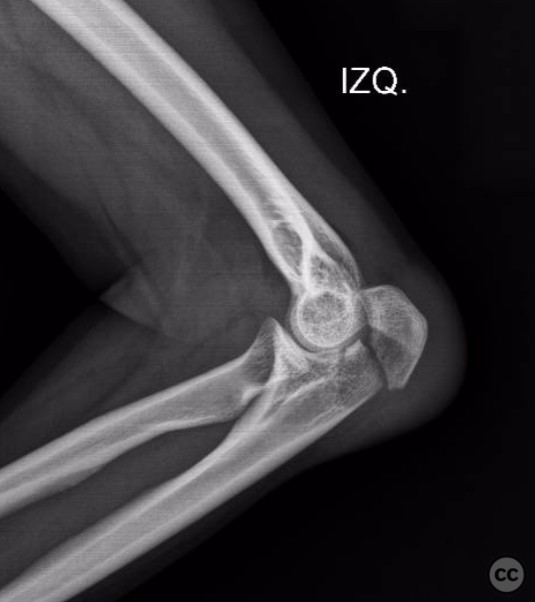

O'Driscoll type II coronoid fracture dis...

Schleswig Holstein, Germany

Ulna - AO/OTA 2Ux